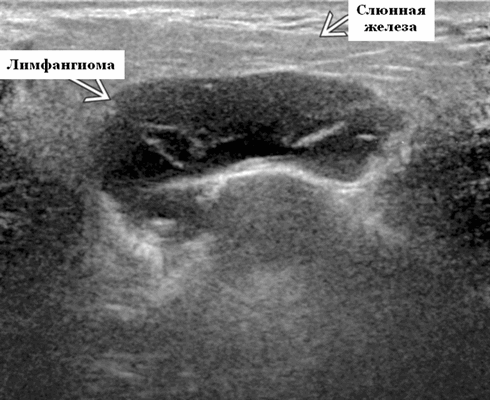

Результаты ультразвукового исследования. Серошкальное УЗИ. Более крупные околоушные лимфангиомы могут быть обнаружены при пренатальном УЗИ. Чаще мультилокулярный, чем монокулярный. Кистозные пространства могут быть округлыми или вкраплениями. Поверхностные поражения сжимаются ультразвуковым датчиком. Внешний вид зависит от того, было ли ранее кровотечение / инфекция. Негеморрагический / неинфицированный лимфаангимоы выглядят на УЗИ как однокамерные или многокамерные (чаще) анэхогенные сжимаемые кисты с тонкими стенками и промежуточными септами. Несмотря на большие размеры, существенного масс эффекта нет. Тонкие незаметные стенки с задним акустическим усилением. Цветной допплер: в области поражения нет кровеносных сосудов. Геморрагический / инфицированный тип лимфатической мальформации. Однокамерные или многокамерные гетерогенные кисты с неровными стенками, внутренним дебрисом. Несжимаемые датчиком и гипоэхогенные полости с толстыми стенками и перегородками. Уровни жидкости-жидкости из-за осаждения и разделения жидкостей предполагают предшествующее кровотечение. Цветной допплер: при заражении; васкуляризация может быть видна в стенках, перегородках и прилегающих мягких тканях